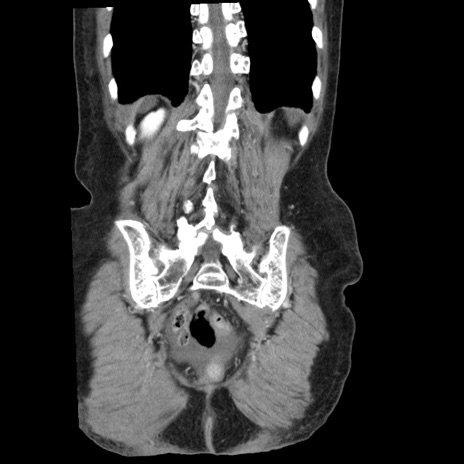

症例1(冠状断像)

【症例】80歳代女性

【主訴】腹痛

【現病歴】8時間前から腹痛あり来院。

【既往歴】糖尿病、脂質異常症、子宮体癌にて子宮全摘術

【身体所見】意識清明・会話良好だが腹痛で苦悶様、全腹部にわたって反跳痛と圧痛あり

【データ】WBC 13600、CRP 0.14、LDH 224、CK 90